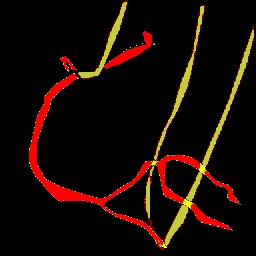

X-ray angiography is the most used imaging modality to visualise blood vessels for interventional purposes such as stenting of stenosed vessels or for diagnostic purposes such as assessment of myocardial perfusion or stenosis grading. To minimise ionising radiation exposure of the patient and medical personnel during image acquisition, low power X-Rays are used resulting in noisy and low contrast images. In the context of diagnosis, the main object of interest is the vascular tree, its branchings and variations in thickness. It is therefore necessary to accurately highlight the vessels in consecutive frames to reduce the noise and improve contrast. In addition, in interventional procedures, identifying interventional instruments (catheter, wires) is also needed in order to better plan and control their positioning. Efficiently discriminating between instruments and vessels as well as other anatomical structures that may have similar appearance is crucial during the interventions. Figure 1(a-c) shows an example of an angiogram sequence. Note large non-rigid motion between frames as well as the ambiguity between vessels and the catheter. Figure 1(e) shows a frame from a different sequence of the same patient but taken at different scan and angle and (f) shows a different patient. There is a significant difference in vessel as well as catheter locations in all three sequences, which we consider as independent examples. Figure 1(d) shows the ground truth segmentation of the first frame.

Using the approach discussed in section 3.2 we automatically generated annotations for 3000 randomly selected frames from sequences different than those with manual ground truth. In order to highlight the difference between the manual and automatic segmentation we present both in figure 4. The ground truth mask includes three labels i.e. background (black), vessel tree (red), and catheter (yellow). Black top-hat based segmentation mask contains significant noise, boundary irregularities and large parts of vessels as well as catheter are missing. The masks filtered with connected components seem to reduce the amount of noise but also further remove some small valid segments. This is crucial when comparing quantitative results of this simple segmentation method with and without connected component filter in Section 4.2.

3000 pairs of frames with their optical flow from the automatically generated dataset were used to train the binary U-Net and the Siamese U-Net models presented in Sections 3.1 and 3.3. As illustrated in Figure 4(f) the Siamese U-Net is more accurate than the baseline U-Net. U-Net fine-tuned with manually annotated and augmented data provides masks with less noise and smooth object boundaries, although the same segments are successfully extracted in both, unsupervised Siamese U-Net and the fine-tuned one.